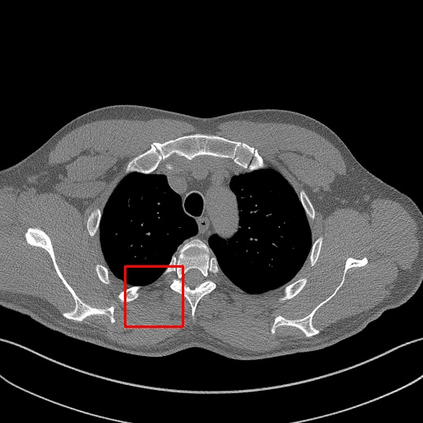

Low-Dose Computed Tomography (LDCT) technique, which reduces the radiation harm to human bodies, is now attracting increasing interest in the medical imaging field. As the image quality is degraded by low dose radiation, LDCT exams require specialized reconstruction methods or denoising algorithms. However, most of the recent effective methods overlook the inner-structure of the original projection data (sinogram) which limits their denoising ability. The inner-structure of the sinogram represents special characteristics of the data in the sinogram domain. By maintaining this structure while denoising, the noise can be obviously restrained. Therefore, we propose an LDCT denoising network namely Sinogram Inner-Structure Transformer (SIST) to reduce the noise by utilizing the inner-structure in the sinogram domain. Specifically, we study the CT imaging mechanism and statistical characteristics of sinogram to design the sinogram inner-structure loss including the global and local inner-structure for restoring high-quality CT images. Besides, we propose a sinogram transformer module to better extract sinogram features. The transformer architecture using a self-attention mechanism can exploit interrelations between projections of different view angles, which achieves an outstanding performance in sinogram denoising. Furthermore, in order to improve the performance in the image domain, we propose the image reconstruction module to complementarily denoise both in the sinogram and image domain.